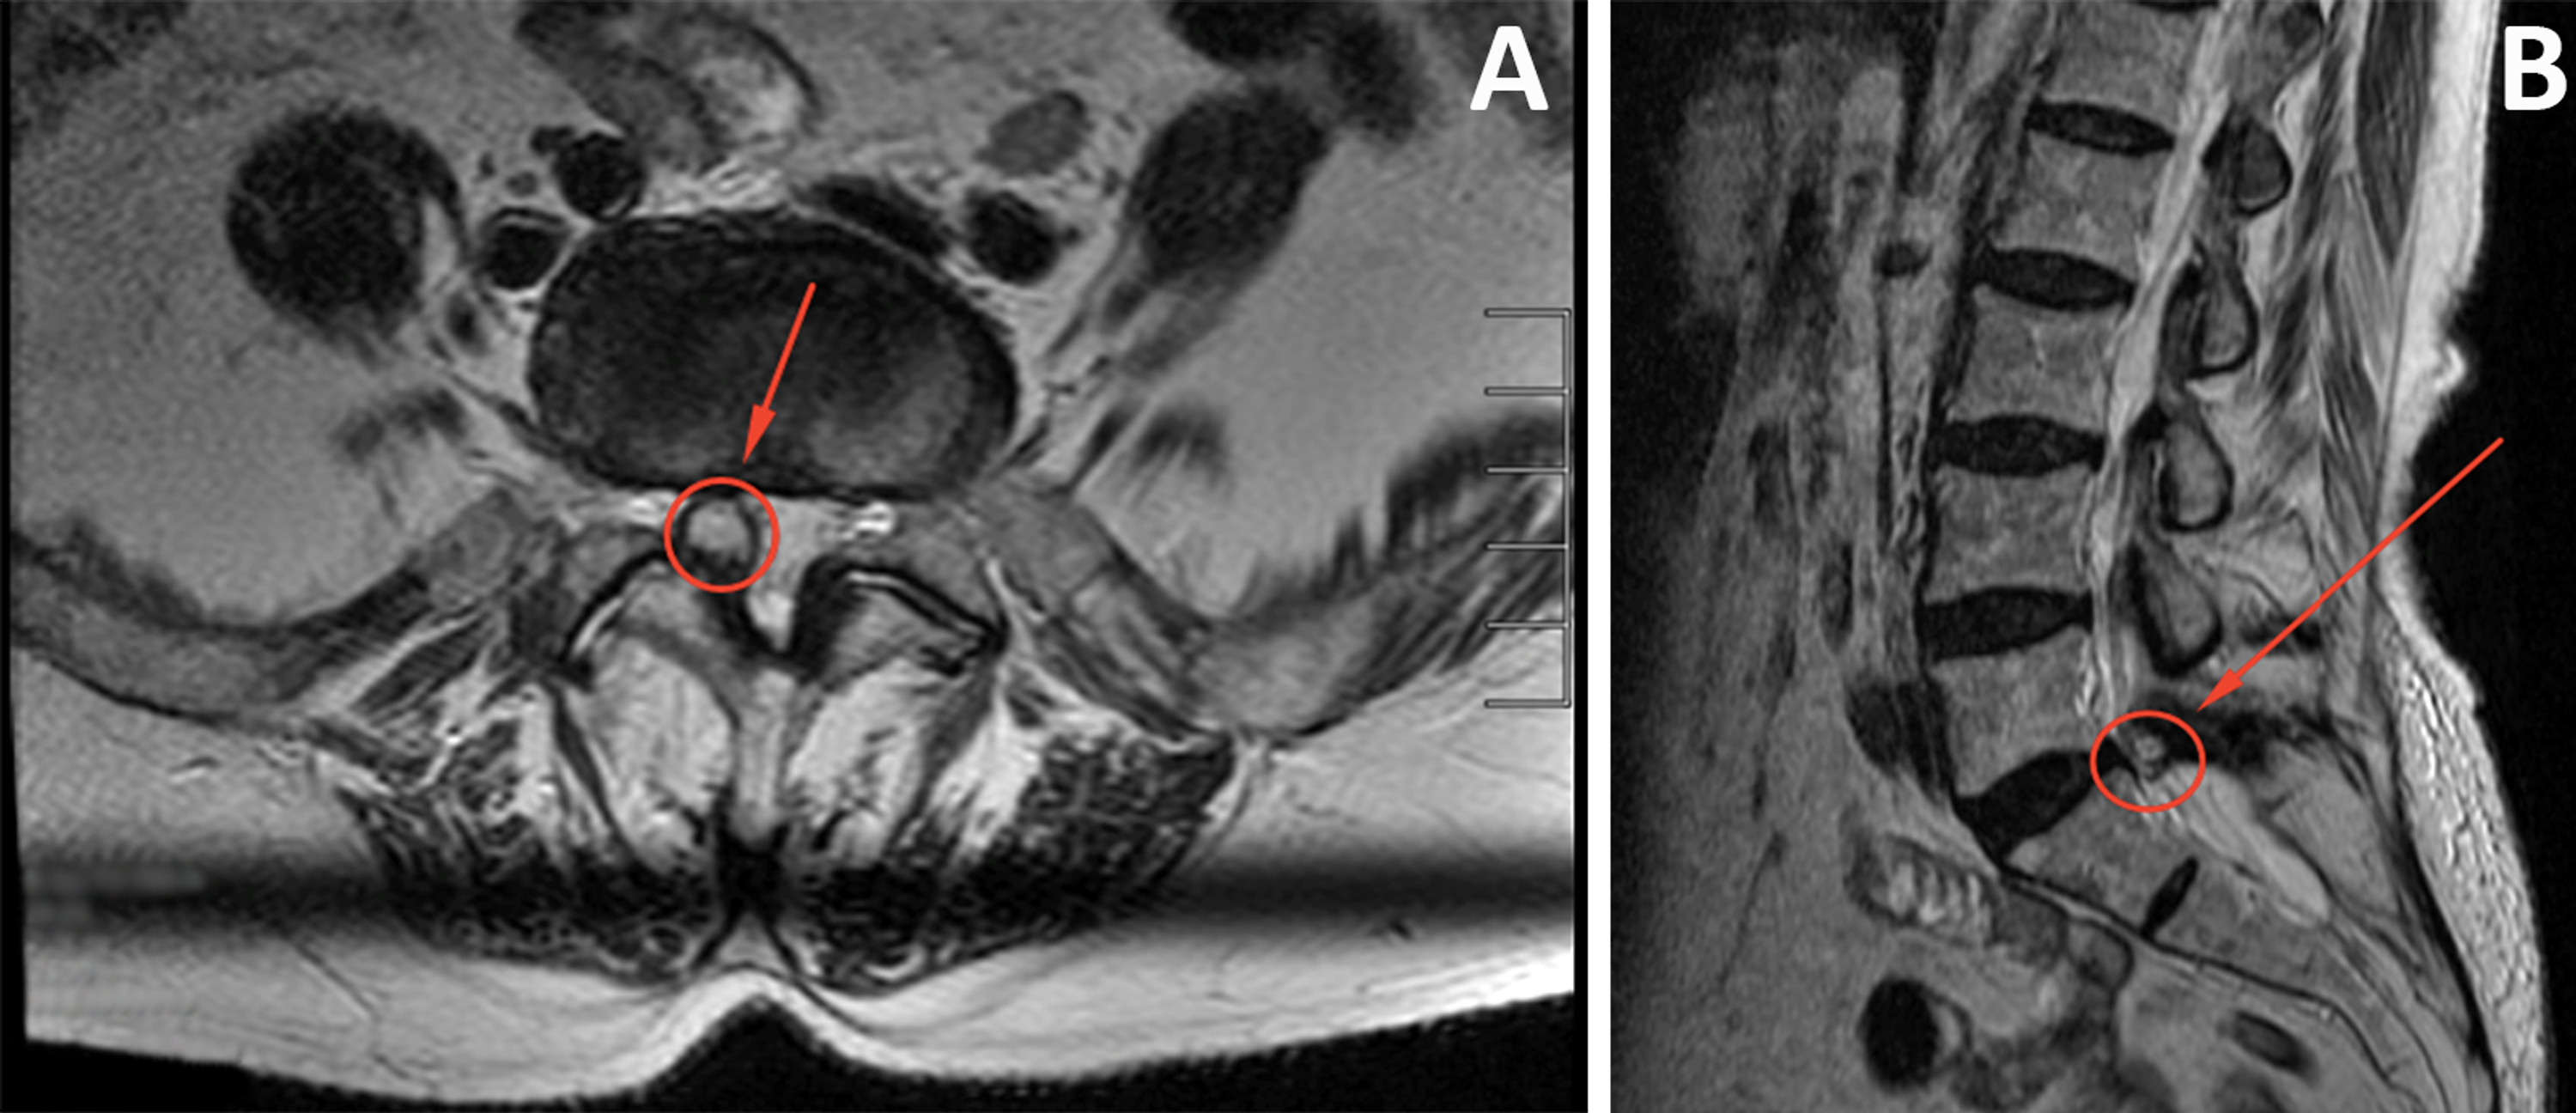

FACET SYNOVIAL CYST RADIOLOGY MRI LUMBAR SPINE Radedasia Facet Joint Cyst  They can cause pain, nerve compression, and other spinal conditions. Learn how they are diagnosed and treated with lifestyle changes, procedures, or surgery. It can cause spinal stenosis. Find out the symptoms, risk factors, diagnosis and treatment options for spinal cysts. Find out the diagnosis, treatment,.  learn about spinal cysts, benign lumps caused by fluid buildup in joints or. Facet Joint Cyst.